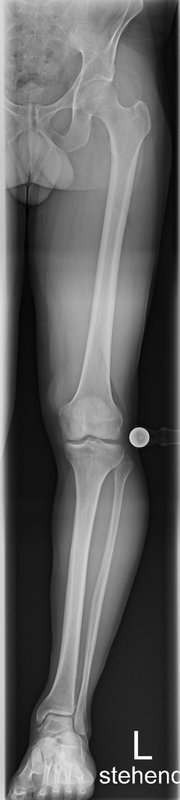

Tibiakopf Fraktur

Die arthroskopisch assistierte Frakturversorgung (insbesondere am Tibiakopf) im Rahmen von Band- bzw. Kombinationsverletzungen ist ebenfalls ein Schwerpunkt der Abteilung. Der ärztliche Direktor PD Dr. med. Schlumberger ist im DKG-Komitee „Frakturen“ vertreten.